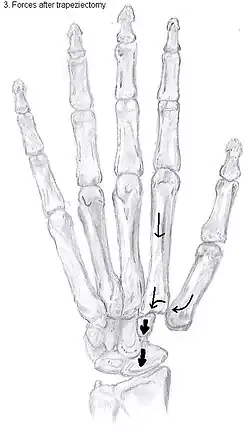

Trapeziectomy

During trapeziectomy,[30] the trapezium bone is removed without any further surgical adjustments. The trapezium bone is removed through an approximately three centimeter long incision along the lateral side of the thumb. To preserve surrounding structures, the trapezium bone is removed "by splitting" it into pieces.

An empty gap is left by the trapeziectomy and the wound is closed with sutures. Despite this gap, no significant changes in function of the thumb are reported.[27] After the surgery, the thumb will be immobilized with a cast.

Trapeziectomy with ligament reconstruction

Another technique is used to reconstruct the volar beak ligament after trapeziectomy. The rationale is that ligament reconstruction(LR) helps maintain the gap between the metacarpal and the scaphoid, and that a larger gap is associated with greater comfort and capability.[32] Again these possibilities are not supported by experimental evidence.

During this procedure the anterior oblique ligament is reconstructed using the FCR tendon. There is a wide variety in techniques to perform this LR, but they all have a similar goal.